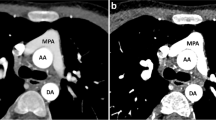

CT images showed incomplete opacification of the hypoplastic left pulmonary artery (Fig. 2), resulting in incomplete evaluation of possible PE in the left pulmonary artery. The Fontan pathway and right main pulmonary artery were patent. Because of the possibility of PE in the left main pulmonary artery, an echocardiogram was immediately obtained after CT examination. The echocardiogram showed patent main pulmonary arteries and Fontan pathway without evidence of PE. The boy’s chest pain eventually resolved and he was discharged home in stable condition the next day.

A 10-year-old boy with complex congenital heart disease who had undergone a lateral Fontan procedure presented with chest pain and elevated D-dimer level. Enhanced axial CT image shows incomplete opacification of the hypoplastic left main pulmonary artery (arrows) with contrast agent resulting in incomplete evaluation of possible PE in the left main pulmonary artery. A subsequently obtained echocardiogram showed a patent left main pulmonary artery

CT images were mildly limited by a beam hardening artefact resulting from multiple intrathoracic embolization coils; however, it was diagnostic for evaluation of thrombosis in the Fontan pathway and PE in the pulmonary arteries. The Fontan pathway and pulmonary arteries were well opacified with intravenous contrast agent without evidence of thrombus or PE (Fig. 5). Based on the CTPA findings, the girl was not subsequently treated with anticoagulation therapy and her symptoms eventually resolved spontaneously.

A 2-year-old girl with complex congenital heart disease including dextrocardia and pulmonary atresia status who had undergone a Fontan procedure presented with shortness of breath and desaturation. CTPA was performed with simultaneous upper- and lower-limb injections of contrast agent for evaluation of PE. Enhanced axial CT image demonstrates patent right (arrow) and left (curved arrow) main pulmonary arteries. Also noted is a metallic artefact from embolization coils